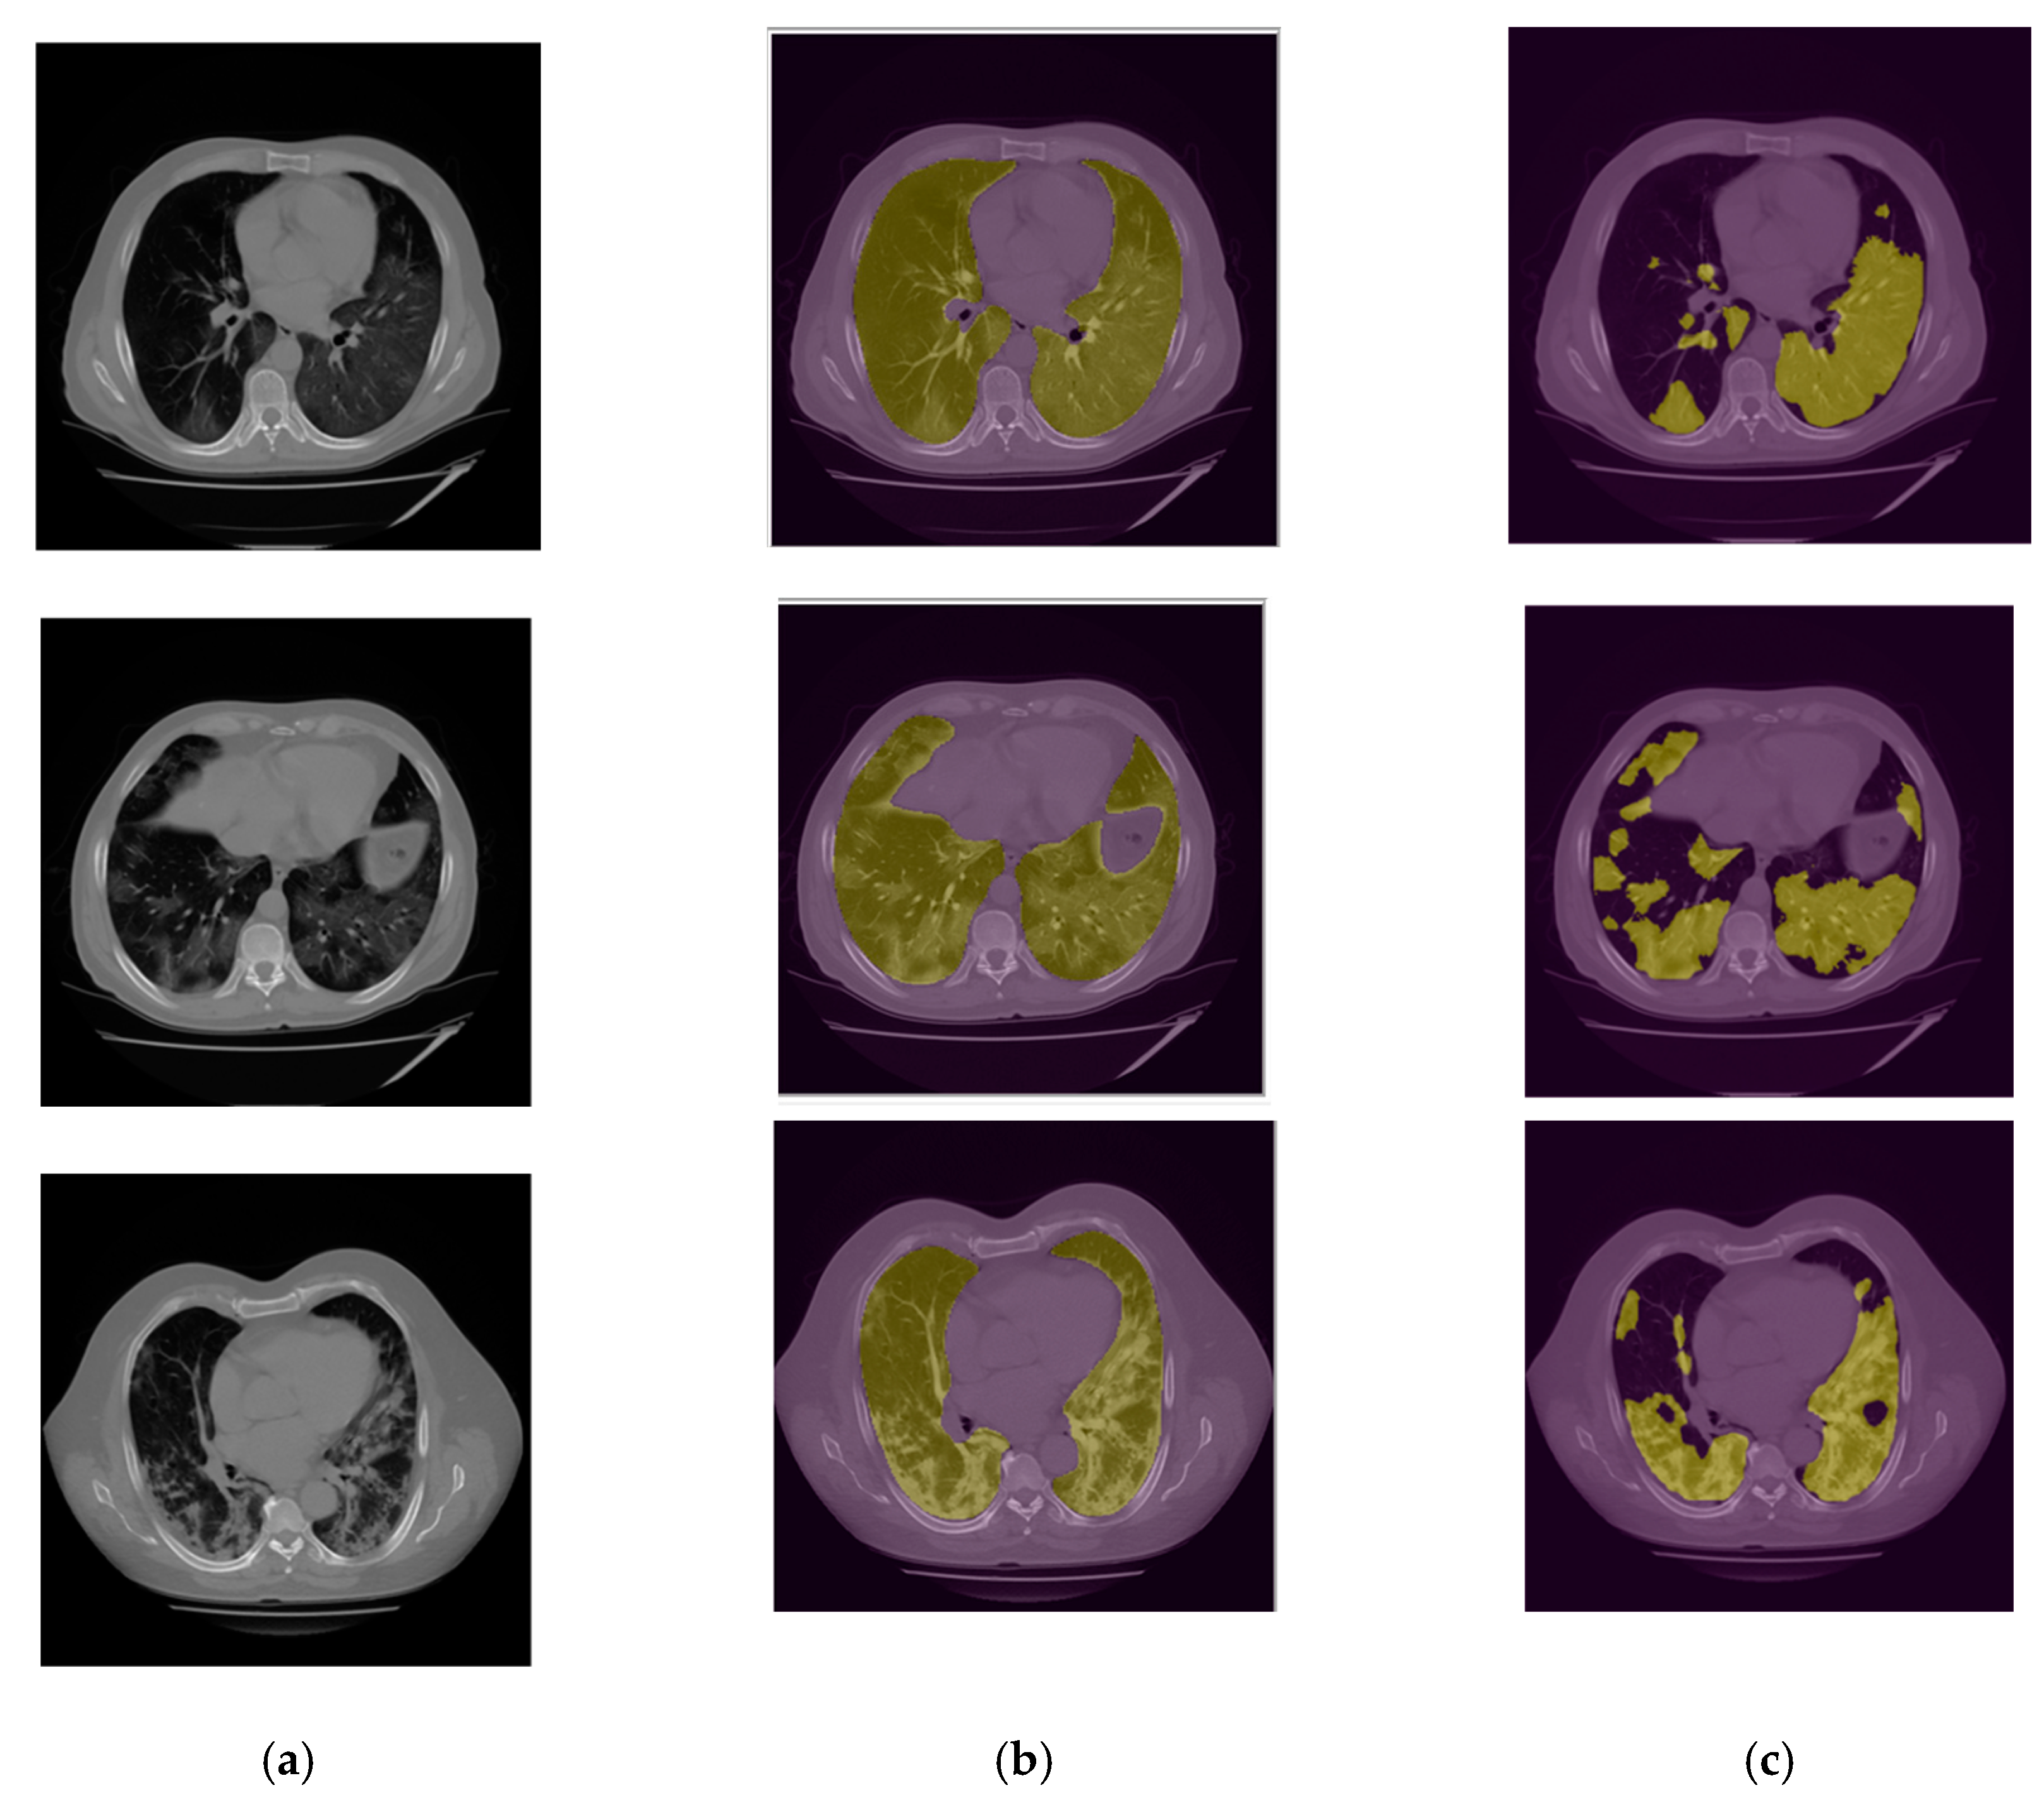

2.3.2. Infection Area Segmentation

3. Results